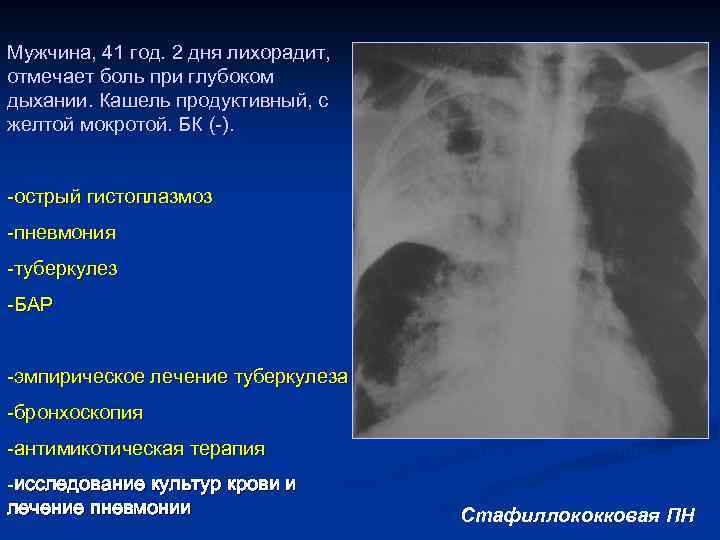

Мужчина, 41 год. 2 дня лихорадит, отмечает боль при глубоком дыхании. Кашель продуктивный, с желтой мокротой. БК (-). -острый гистоплазмоз -пневмония -туберкулез -БАР -эмпирическое лечение туберкулеза -бронхоскопия -антимикотическая терапия -исследование культур крови и лечение пневмонии Rg – инфильтративные изменения неоднородного х-ра, с-м «воздушной БГ, полости распада, вовлечение в процесс средней доли. Стафиллококковая ПН